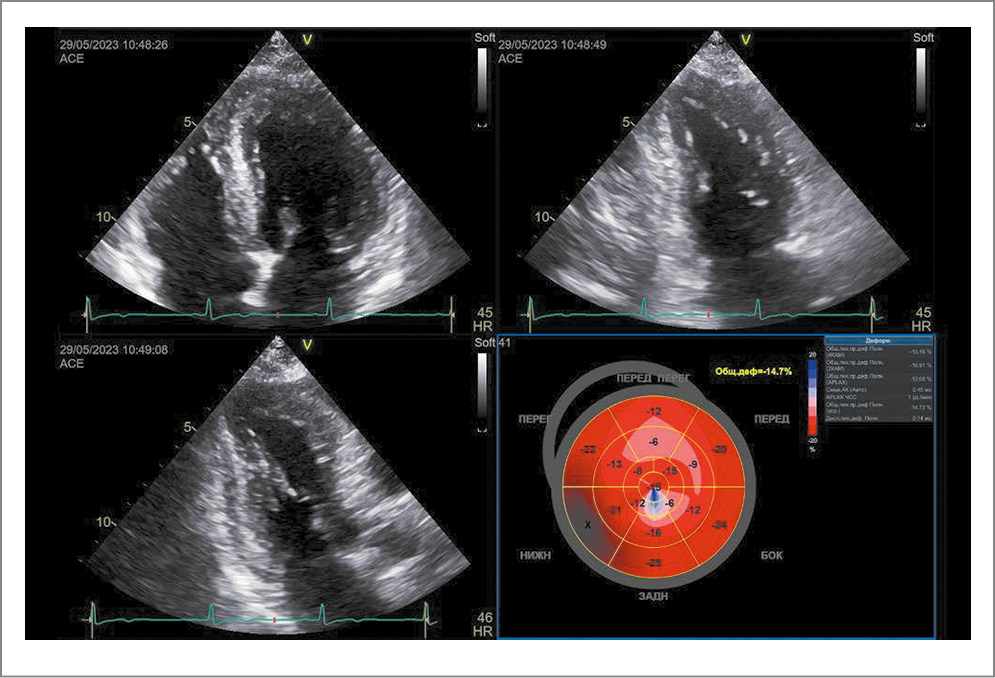

По данным ЭхоКГ – положительная динамика в виде увеличения ФВ ЛЖ до 59% (по Simpson). Сохранился гипокинез апикальных сегментов передне-перегородочной стенки и межжелудочковой перегородки, в остальных сегментах отмечался нормокинез. Регистрировалась положительная динамика показателя GLS: уменьшение с -11,2% до -14,5%, при норме менее -15% (рис. 8).

Рис. 8. Эхокардиограмма на 10-е сутки госпитализации.

По результатам ЭхоКГ глобальная сократительная функция миокарда ЛЖ удовлетворительная. ФВ ЛЖ составила 63%, GLS – -14,7%, конечный диастолический размер ЛЖ – 4,7 см, КДО ЛЖ – 82 мл, конечный систолический размер ЛЖ – 3,1 см, КСО ЛЖ – 29 мл. Определялся локальный незначительный гипокинез апикального сегмента передне-перегородочной стенки (рис. 10).

Рис. 10. Эхокардиограмма через 1 мес после выписки из стационара.